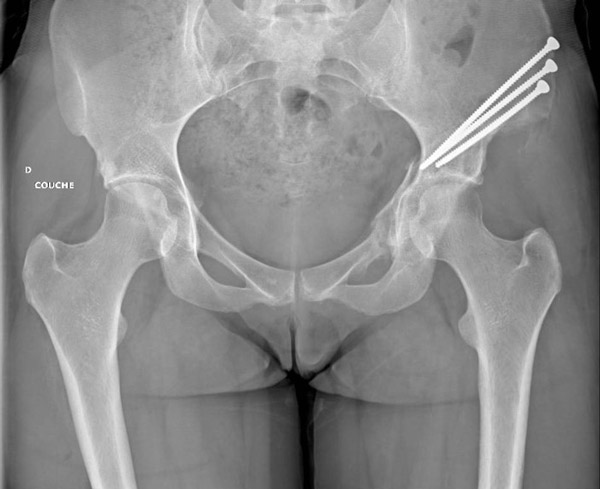

What is your surgical management?

✔️Anteverting Peri Acetabular Osteotomy

Anteverting Peri Acetabular Osteotomy

Anteverting/reverse PAO

Anteverting Pariacetabular Osteotomy fo Symptomatic Acetabular Retroversion